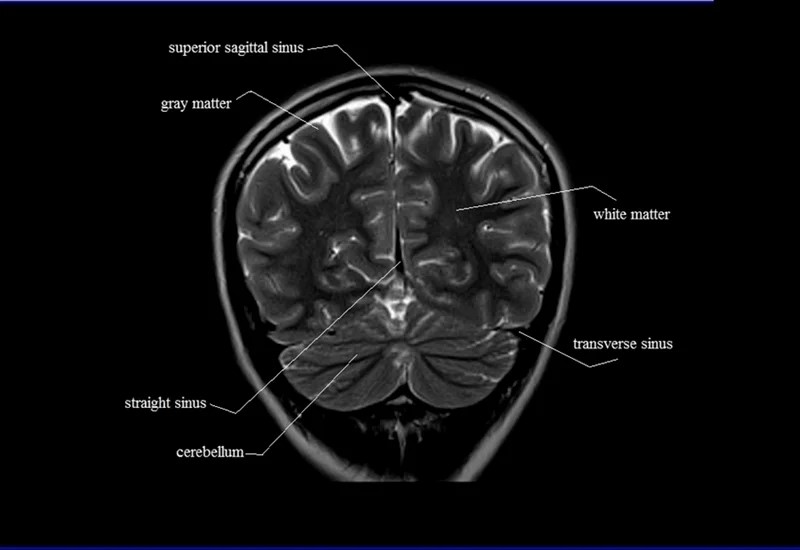

MRI Coronal Cross Sectional Anatomy of Brain

This MRI brain cross-sectional anatomy tool is absolutely free to use. Use the mouse scroll wheel to move the images up and down, or alternatively, use the tiny arrows (→) on both sides of the image to navigate through the images.